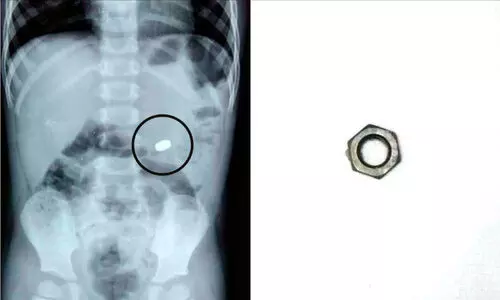

തൊടുപുഴ: മൂന്ന് വയസ്സുകാരന്റെ ആമാശയത്തിൽ കുടുങ്ങിയ ഇരുമ്പ് നട്ട് പുറത്തെടുത്തു....